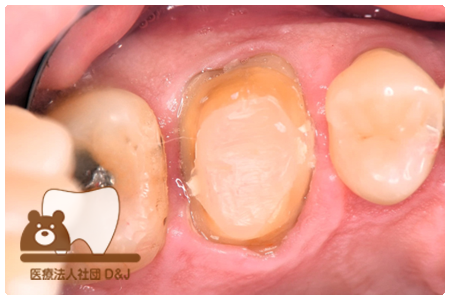

症例4フルジルコニアクラウン 左下6

治療前

治療後

37歳 男性

- 治療内容

- 以前のクラウンがセメントの劣化により外れた為その上にフルジルコニア製の被せ物を装着しました。見た目と強度を両立した自由診療の治療です。

- 治療期間

- 1カ月

- 費用

- 自費

フルジルコニアクラウン:77,000円(税込)

(R8.1月時点)

- その他の治療の費用は含まれておりません。

- リスク・副作用

- 硬い素材のため、かみ合う歯に負担がかかることがあります。将来取り外す場合に歯に負担がかかることがあります。強い力が加わると、まれに欠けたり割れたりすることがあります。